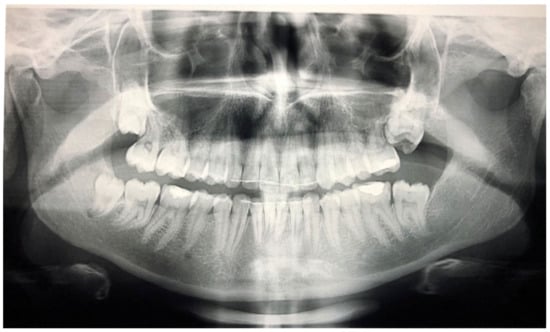

The phenomenon where molars cease to erupt before they emerge, without a physical barrier in the eruption path or as a consequence of an atypical location, is defined as primary retention. The alveolar support of a primarily retained molar, which does not resorb occlusally, is considered a normal barrier to the eruption path. Primary retention is similar to “unerupted” and “embedded” teeth [9]. In the event that the eruption of a permanent tooth is at least 2 years delayed compared to what is normally expected, primary retention should be a clinical entity to take into account. A radiographical follow-up of a minimum of 6 months is suggested as an initial control to determine whether the tooth is showing any eruptive movement or not [10]. The suggested radiographic methods include a periapical or even panoramic X-ray. Primary retention is the possible result of a disturbance in the dental follicle that does not succeed in initiating the metabolic events responsible for bone resorption in the eruption traject [11] (Figure 1 and Figure 2).

Figure 1.

Patient presenting eruption failure of the upper left second molar due to primary retention.

Figure 2.